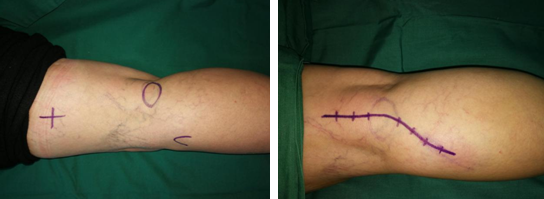

陈步国、吴尧、吴贞志手术团队为王大妈进行了肿物切除手术。术中探查发现一直径约2.8cm的球体肿物,质硬,而神经横穿肿物内侧。手术团队游离肿物外膜,予肿物周围切断神经,完整切除肿物。最后,吻合神经外膜,缝合皮下组织和伤口。

手术很顺利,肿物术后送病理检查,诊断结果示该肿物为神经鞘瘤。